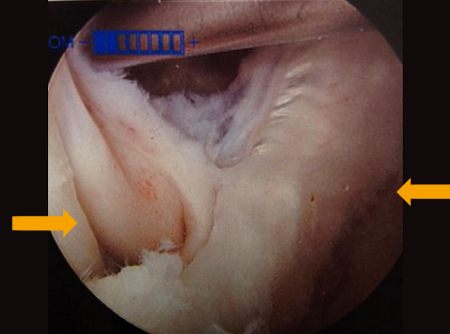

One study demonstrated that popliteal cysts develop from lack of external anatomical support.[1] This area is found between the two expansions of the semimembranosus muscle and the medial gastrocnemius.[Figure caption and citation for the preceding image starts]: MRI depicting cyst in interval of medial gastrocnemius and semimembranosusFrom the collection of Dr John D. Kelly IV; used with permission [Citation ends].

[Figure caption and citation for the preceding image starts]: Interval of medial gastrocnemius and semimembranosus viewed with arthroscopeFrom the collection of Dr John D. Kelly IV; used with permission [Citation ends].